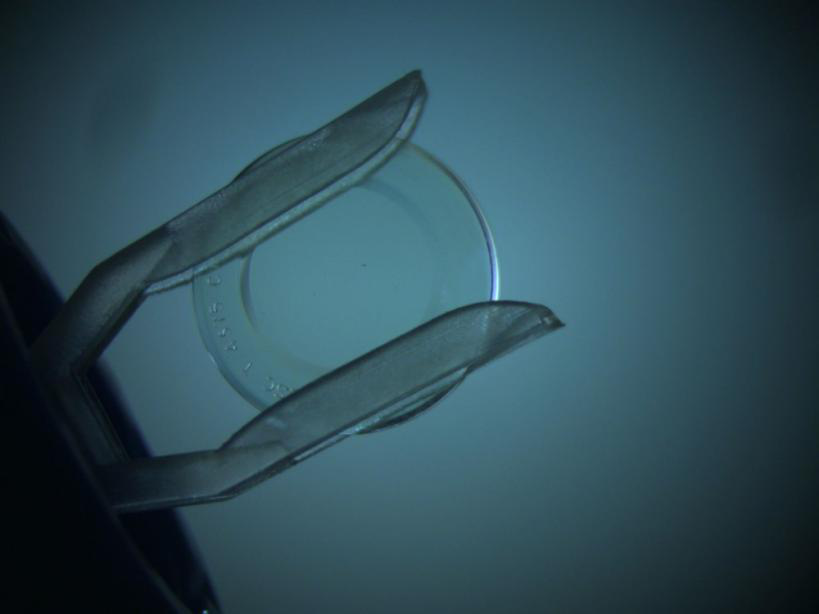

昆明华山眼科医院青少年近视防控专家、小儿眼病及视光专科专科主任孙建沙介绍,角膜塑形镜是一种在夜晚佩戴的透气性硬质角膜接触镜。通过中央区域逆几何设计,能为我们眼睛前表面角膜“塑形”,从而暂时性的降低近视度数,达到提高裸眼视力的效果。最重要的是,大量国内外研究显示,通过这种方法能有效控制青少年近视的增长速度。只需晚上睡觉时配戴,白天无需戴镜,即可保持一天清晰的裸眼视力。长期佩戴,就能有效控制住青少年近视的发展,实现近视防控的目的。